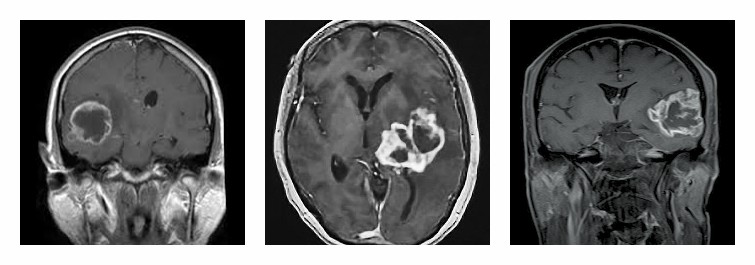

Το γλοίωμα είναι όγκος εγκεφάλου που αναπτύσσεται από τα νευρογλοιακά κύτταρα (τα κύτταρα που περιβάλουν τους νευρώνες). Είναι από τους πιο συχνούς όγκους του εγκεφάλου και εκδηλώνεται κλινικά με ποικίλα συμπτώματα όπως: κεφαλαλγία, ναυτία, έμετο, επιληπτικές κρίσεις, διαταραχές όρασης/ομιλίας/ακοής/κατάποσης, αστάθεια βαδίσεως κ.ά. Ανάλογα με το είδος των νευρογλοιακών κυττάρων από τα οποία προέρχονται διακρίνονται σε αστροκυτώματα, ολιγοδενδρογλοιώματα, επενδυμώματα ή σε μικτούς όγκους όπως τα ολιγοαστροκυτώματα. Με βάση την βιολογική τους συμπεριφορά διακρίνονται σε χαμηλού (I, II) ή υψηλού βαθμού (III, IV) κακοήθειας, που καθορίζει και την ταχύτητα με την οποία αναπτύσσονται αλλά και την πρόγνωσή τους. Η διάγνωση των γλοιωμάτων γίνεται κυρίως με την μαγνητική τομογραφία, ενώ η θεραπεία τους είναι κατά βάση χειρουργική και συνδυασμός ακτινοθεραπείας ή/και χημειοθεραπείας, όπου ενδείκνυται.